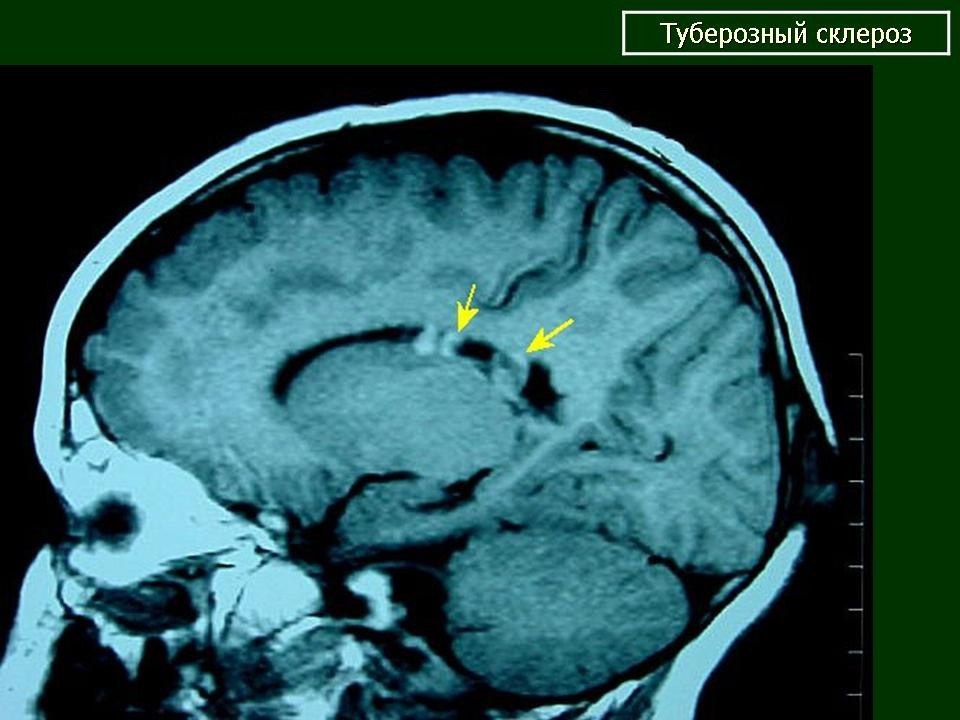

🧠 15 мая — День осведомлённости о туберозном склерозе

Туберозный склероз — это генетическое заболевание, которое вызывает рост *доброкачественных опухолей* во многих органах: мозге, почках, сердце, коже, лёгких.